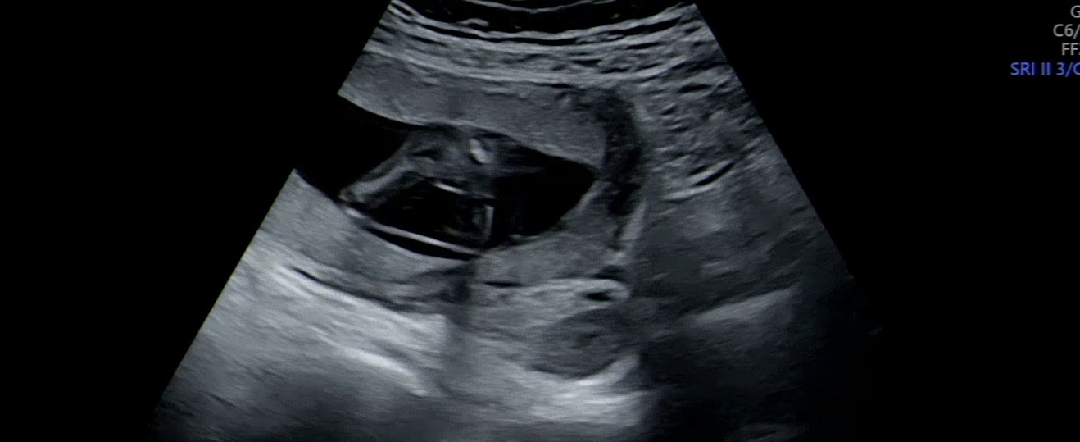

아기 다리사이 보이시나요?

탯줄이 다리사이에 있긴한데... 그거말고는 아무것도 보이지않아요 ㅈㄲ맘에게 아들이라고 들어서 맘먹고잇엇는디 ㅋㅋㅋ 띠용하네요 ㅠㅠ